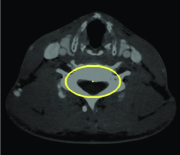

Appearance is one of the most important visual cues to distinguish between different structures in an image. Appearance is described by studying the distribution of different features such as intensity values in gray-scale images, color, and texture inside each object. In most cases, appearance models are incorporated into the data term in (2) and (7). The purpose of incorporating appearance prior is to fit the appearance distribution of the segmented objects to the distribution of objects of interest, e.g. using Gaussian mixture model (GMM) (Rother et al., 2004). In the literature, there are two ways to model the appearance: 1) adaptively learning the appearance during the segmentation procedure, and 2) knowing the appearance model prior to performing segmentation (e.g. by observing the appearance distribution of the training data). In the former case, the appearance model is learned as the segmentation is performed (Vese and Chan, 2002) (computed online). In the second case, it is assumed that the probability of each pixel belonging to particular label is known, i.e. if represents a particular set of feature values (e.g. intensity/color) associated with each image location for object, then it is assumed that is known (or pre-computed offline). This probability is usually learned and estimated from the distribution of features inside small samples of each object. Figure 9 illustrates the probability of different structures (the kidney, the tumour, and the background) in an endoscopic scene. A lower intensity in Figures 9(b-d) corresponds to higher probability.